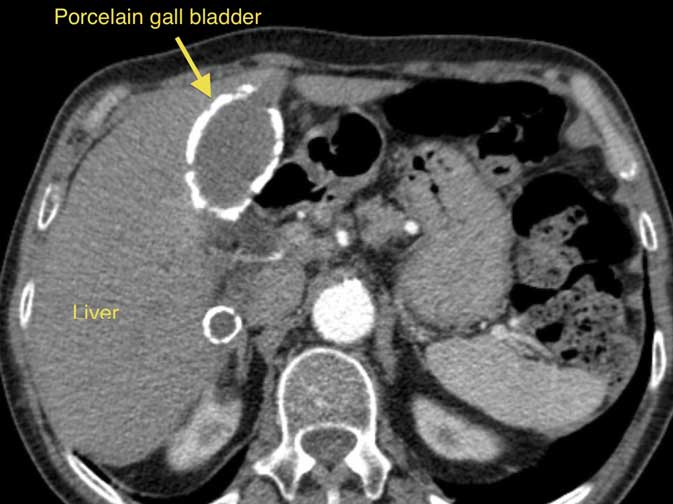

Calcium deposits in the wall of the gall bladder (a consequence of chronic inflammation), described as Porcelain gall bladder, increase the risk of gall bladder cancer. The picture on this page shows a CT scan, with a porcelain gall bladder clearly visible (you can click on the picture to enlarge it).